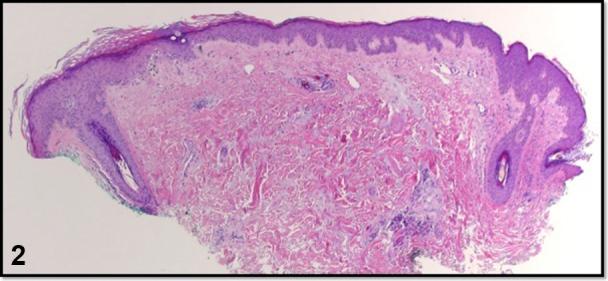

Curvilinear violaceous plaques along Blaschko lines.

Curvilinear violaceous plaques along Blaschko lines.沿布拉斯科线分布的曲线状紫罗兰色斑块。